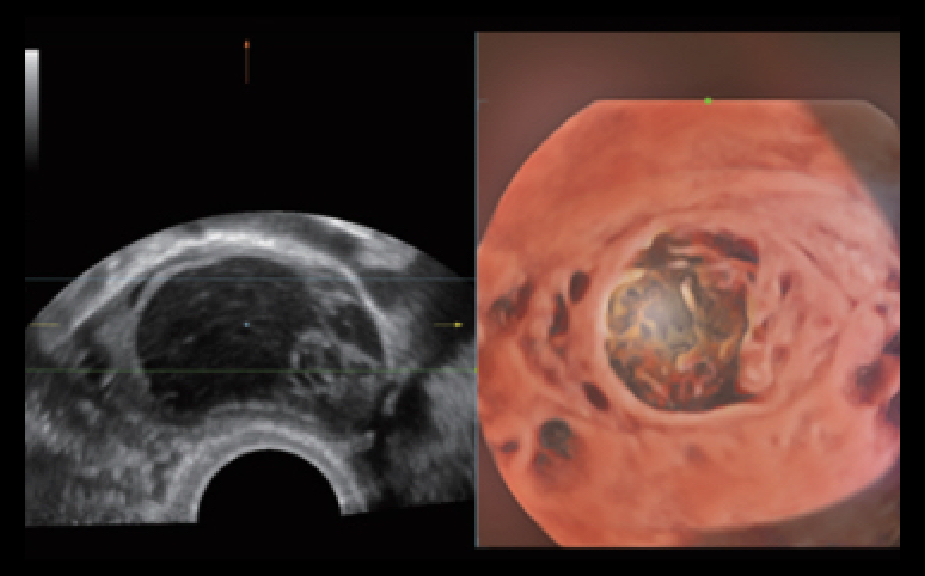

Obrazy kliniczne